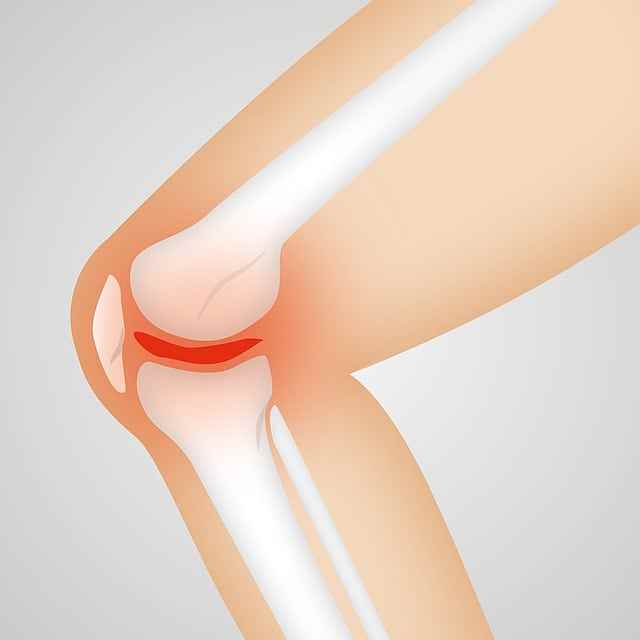

2. 골관절염

무릎 통증의 가장 흔한 원인 중 하나는 연골이 분해되는 것을 특징으로 하는 퇴행성 관절 질환인 골관절염입니다. 연골이 닳으면서 뼈가 서로 마찰되면서 무릎에 통증, 경직, 붓기 등이 생길 수 있습니다.

골관절염